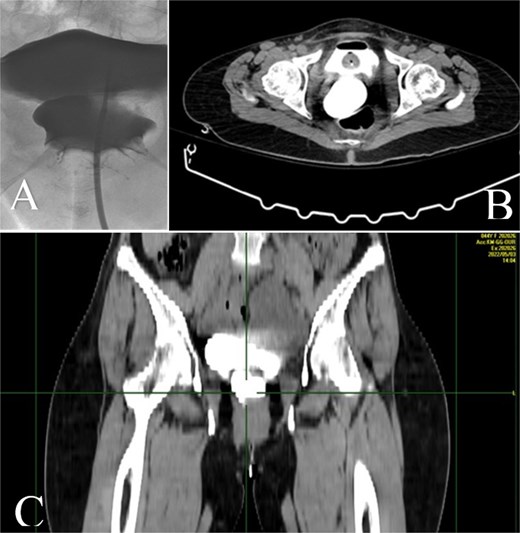

A CT nephrotomography with contrast enhancement was performed and identified an abnormal communication between the right ureter and the vagina reporting an UVF (Fig. 1). Moreover, a retrograde cystography was also performed without any findings. Due to the high suspicion of an intraoperative ureteral trauma, a conservative management was decided and a percutaneous nephrostomy was placed in the right kidney, aiming to prevent further urinary leakage from the vagina and to avoid further dilation of the kidney.

A: Diagnostic nephrotomography showing the existence of an UVF. B: CT nephrotomography showing the abnormal passage of intravenous contrast enhancement fluid from the ureter to vagina, confirming the existence of an UVF.